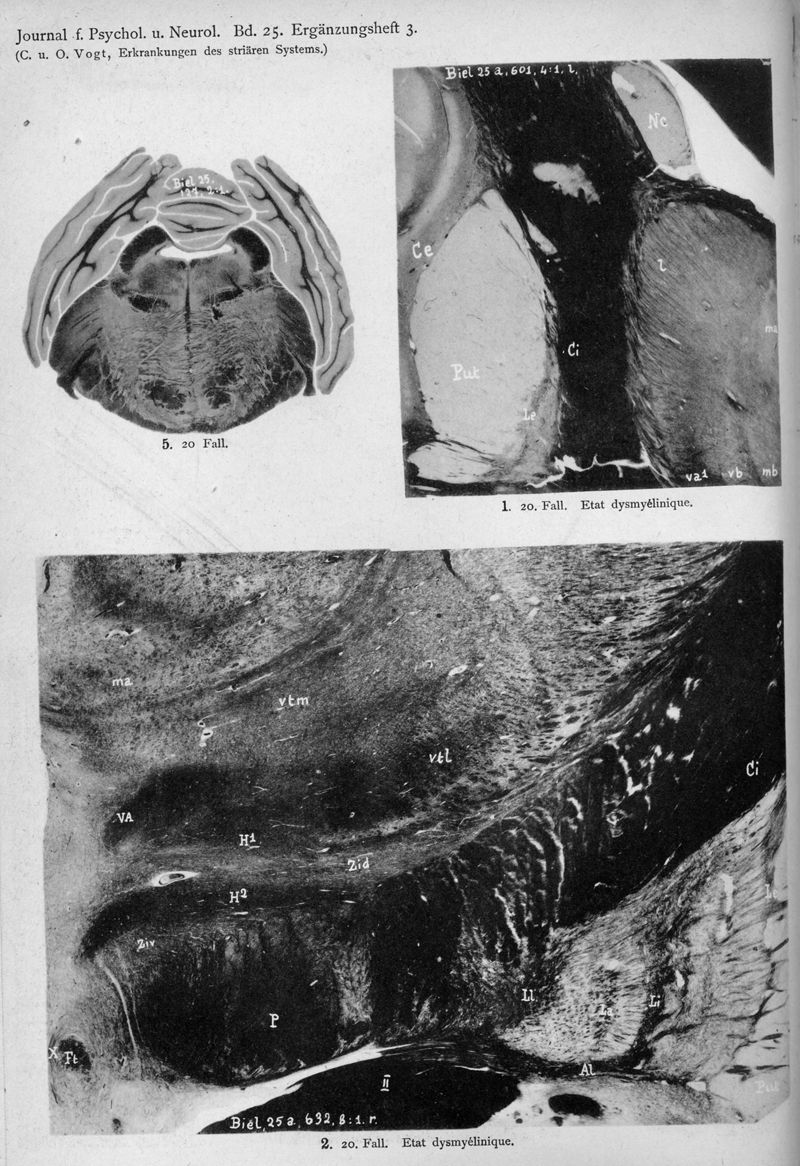

VOGT, Cécile / VOGT, O.

In : Journal für Psychologie und Neurologie,

1920, Vol. 25, pp. 627-846